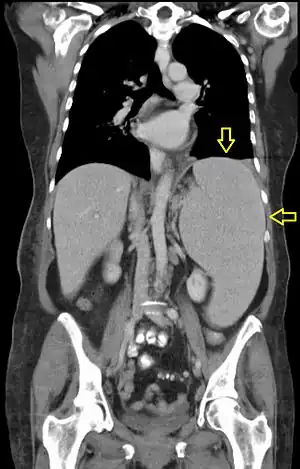

| CT scan in a patient with chronic lymphocytic leukemia, showing splenomegaly. Yellow arrows point at the spleen. | |

Splenomegaly is an enlargement of the spleen.[1] The spleen usually lies in the left upper quadrant (LUQ) of the human abdomen. Splenomegaly is one of the four cardinal signs of hypersplenism which include: some reduction in number of circulating blood cells affecting granulocytes, erythrocytes or platelets in any combination; a compensatory proliferative response in the bone marrow; and the potential for correction of these abnormalities by splenectomy. Splenomegaly is usually associated with increased workload (such as in hemolytic anemias), which suggests that it is a response to hyperfunction. It is therefore not surprising that splenomegaly is associated with any disease process that involves abnormal red blood cells being destroyed in the spleen. Other common causes include congestion due to portal hypertension and infiltration by leukemias and lymphomas. Thus, the finding of an enlarged spleen, along with caput medusae, is an important sign of portal hypertension.[2]